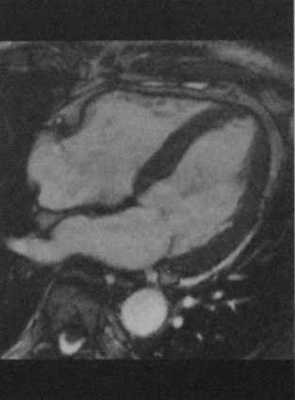

Та же пациентка, что и на рисунке 6.1. МРТ. SSFP-изображение на четырехкамерном срезе демонстрирует выраженную гипертрофию миокарда ЛЖ, преимущественно перегородки.